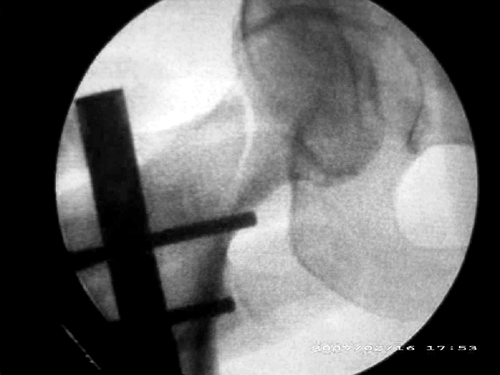

患者,女,因外伤就诊。摄骨盆及右股骨。当时报告骨盆未见明显异常,右股骨中段粉碎性骨折。五天后行股骨中段骨折内固定手术,术中摄床边片示股骨颈骨折。现把术前和术中图像上传。请大家高诊,分析股骨颈骨折是术前漏诊还是其他原因。术前骨盆片右股骨颈显示欠佳是由于股骨中段骨折无法将股骨颈完全显示。

标题: 重叠?

重叠?

回头看术前片,可见一低密透光区.

关于楼主说的骨折线的形态,的确和一般外伤的有种不太一样的感觉,上方裂隙较明显,下方骨皮质“连续”,我认为成年人应该是全部断了的,不全骨折的可能性非常非常小,该片恰好无法全部显示骨折线。骨折线的形态不能判定术前还是术后骨折。以上只是个人小小看法,请各位老师指正为谢!